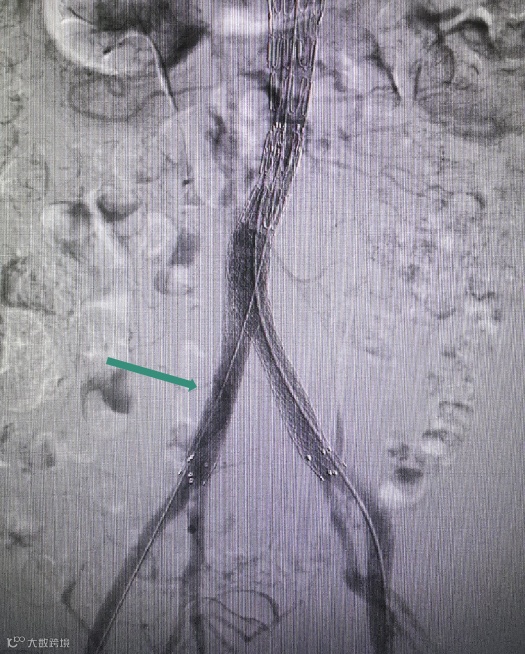

Separator With Aspiration catheter for Mechanical Thrombectomy(MT)【分离器辅助导管抽吸技术】:旨在提高整体系统的抽吸效率和治疗安全性,快速帮助血栓清除。

1)抽吸导管头端堵管,分离器可以快速疏通导管,降低撤管冲洗的频率。

2)针对大负荷血栓或亚急性血栓,分离器辅助下抽吸能提升整体系统抽吸效率,缩短手术时间。

手术过程